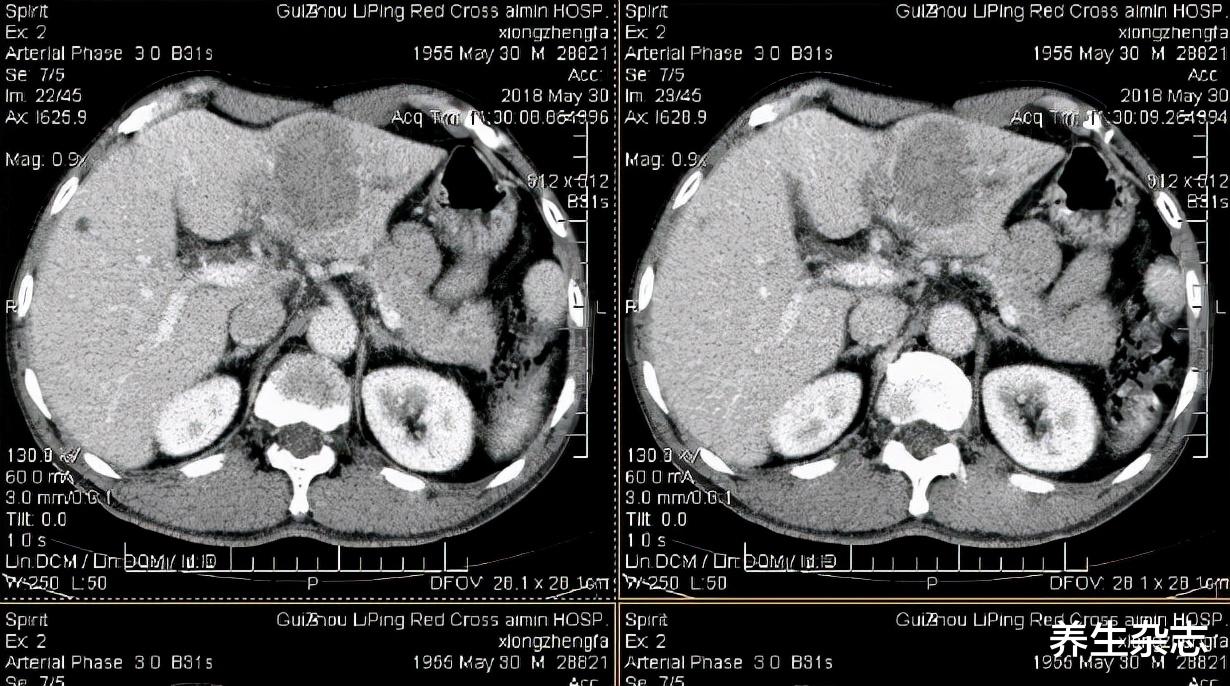

结果却被告知肝脏情况恶化 , “肝硬化已经发展为肝癌了 。 ”